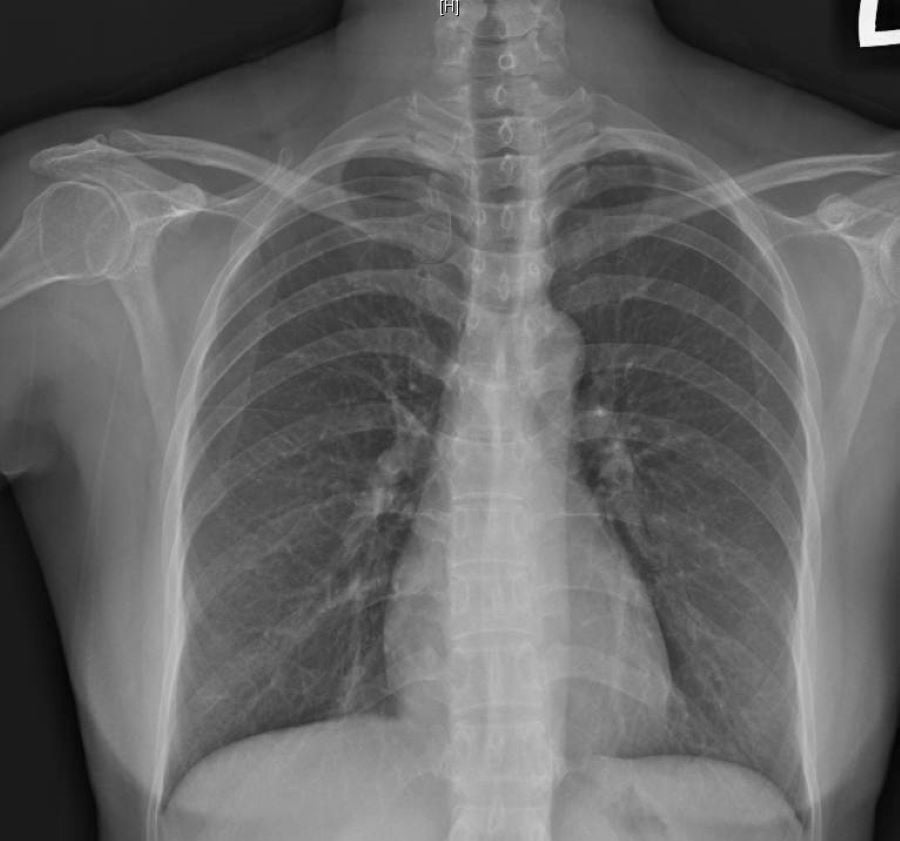

▲61歲家庭主婦的胸腔X片顯示無明顯浸潤或肺炎陰影。

胸腔內科主任蕭惠元醫師指出:每當季節交替、日夜溫差大的時期,一些流感或風寒感冒的患者的發燒、流鼻水等症狀康復後,會有持續一段時間的乾咳,甚至持續超過3週似乎咳嗽難斷根,經X光與肺活量檢查,顯示無明顯浸潤或肺炎陰影,排除肺炎、肺癌或肺結核等重大疾病後,確診為「感染後咳嗽」;經過止咳藥物治療1週左右可痊癒。